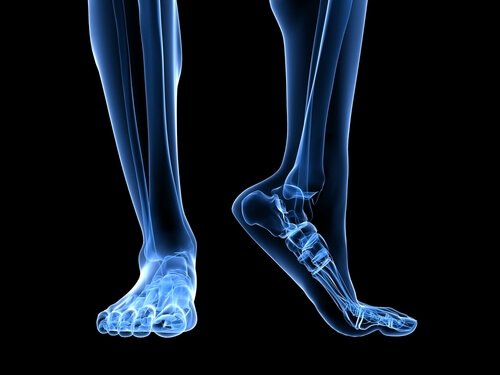

足部解剖學

有幾種解剖學結構在足底筋膜的過度負荷中扮演重要角色。

阿基里斯腱是一條腓腸肌連接跟骨的肌腱。阿基里斯腱的回縮會觸發跟骨的壓力增加,進而導致足底筋膜的壓力增加。

另一個解剖學結構的重要因素是腳掌著地的方式,也就是說,脚是如何接觸地面的。扁平足或者足部有過度內旋的傾向,會伸展足底筋膜,進而增加組織額外壓力而造成撕裂的風險。